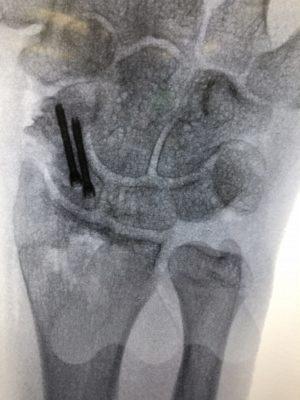

Undisplaced scaphoid waist and distal pole fractures have the best capacity to heal and have a >94% chance of healing even without surgery. They can be managed in a full-time cast or splint for eight weeks. Proximal pole fractures and those that are displaced have a higher risk of the fracture not healing. Proximal pole fractures have a 66% chance of healing by cast treatment and >1mm displacement at the waist, can reduce the healing rate to 73%. In these situations or where full time casting for eight weeks is not desirable, surgical fixation is an option to increase the chance of fracture healing. Depending on the location of the fracture, whether it is fragmented or displaced, will determine how the fracture is fixed. The most common type of fixation is by screw fixation buried inside the bone, inserted through a small incision on the palm near the thumb or back of the wrist.

In situations where scaphoid fractures have been initially missed but identified later, before the onset of arthritis, the diagnosis of a scaphoid non-union is made. These situations often require surgery as the chance of healing by late casting is unlikely to result in fracture healing. The surgery aims to clear out the scar tissue at the fracture site and sometimes add fresh bone from either the wrist or hip to add structural support and fill in defects in the bone and insert a screw for fracture fixation to get the bone to heal and restore normal stability to the wrist. The long term aims are to try and slow the progression towards arthritis in the wrist, however, research studies have shown that this can still develop. In some circumstances where the quality of the bone is poor or has lost it’s blood supply, bone graft with it’s own blood supply is taken from the wrist or knee and connected to the scaphoid.